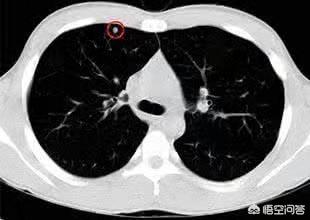

肺結節とは、肺にできる3cm以下の球状の病変のことで、胸部CTが健康診断に普及したことで、肺結節の発見率はどんどん高くなっており、違和感なく肺結節の検査を受けている人も多く、ネット上では「肺がんが怖い」と言われていますが、では結節の大きさはどれくらいなのでしょうか?

私たちはこの病気の診断の考え方を知っており、それから頭に戻って肺結節の話をする。肺結節とは、肺にできる直径3cm以下の円形または不規則な病変のことで、画像上では密度が増加した陰影として現れ、均質または不均一、単発または多発、境界が明瞭または不明瞭である。

肺結節の定義について、中国医学ガイドラインは次のように述べている:画像診断(胸部CT)により、直径3cm以下の限局性、円形状、密度増加した固形または亜固形の肺影が認められ、孤立性または多発性の可能性があり、肺無気肺、肺門リンパ節腫大、胸水を伴わない。

一般に、肺にできる直径3cm以下の密度増加影を肺結節と呼びますが、その危険度は大きさだけでなく、結節の形態、密度、増殖速度も合わせて判断する必要があります。

CT検査以前は、肺結節が発見される確率は0.2%以下であり、発見される結節の大きさは基本的に1cm以上であったが、CT検査の普及に伴い、肺結節が発見される確率は飛躍的に上昇したが、どの程度の大きさの肺結節であれば、あるいはどのような肺結節であれば、より危険なのかが、現在特に関心の高いテーマである。

以下では、肺結節の大きさと良性・悪性のリスクの関係を見分ける方法を紹介する!